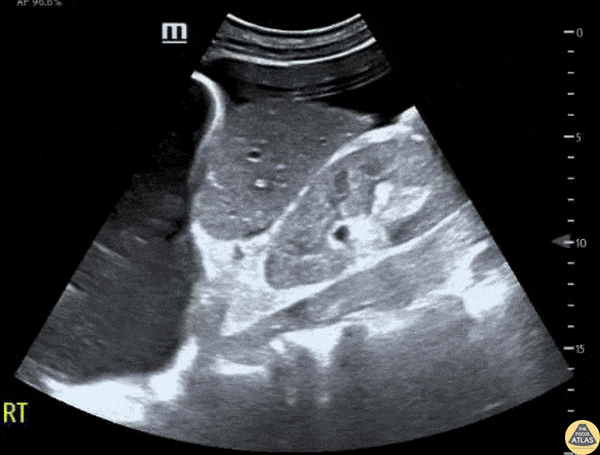

Patient presented to the emergency department with atraumatic acute onset of shortness of breath. An EFAST was performed to evaluate for pneumothorax and assess for free fluid in the abdomen, thorax, and pericardium. A significant right pleural effusion was present. Additionally, US of RUQ demonstrated a liver which appeared small in size with prominent ascites. This demonstrates the utility of POCUS to identify free fluid in a quick and efficient manner as compared to other common studies such as a CT scan, even in non-traumatic patients. Contributors: Lauren Lowes, DO; Krishna Patel, DO; Julia Tu, MS-4 Central Michigan University Residency of Emergency Medicine